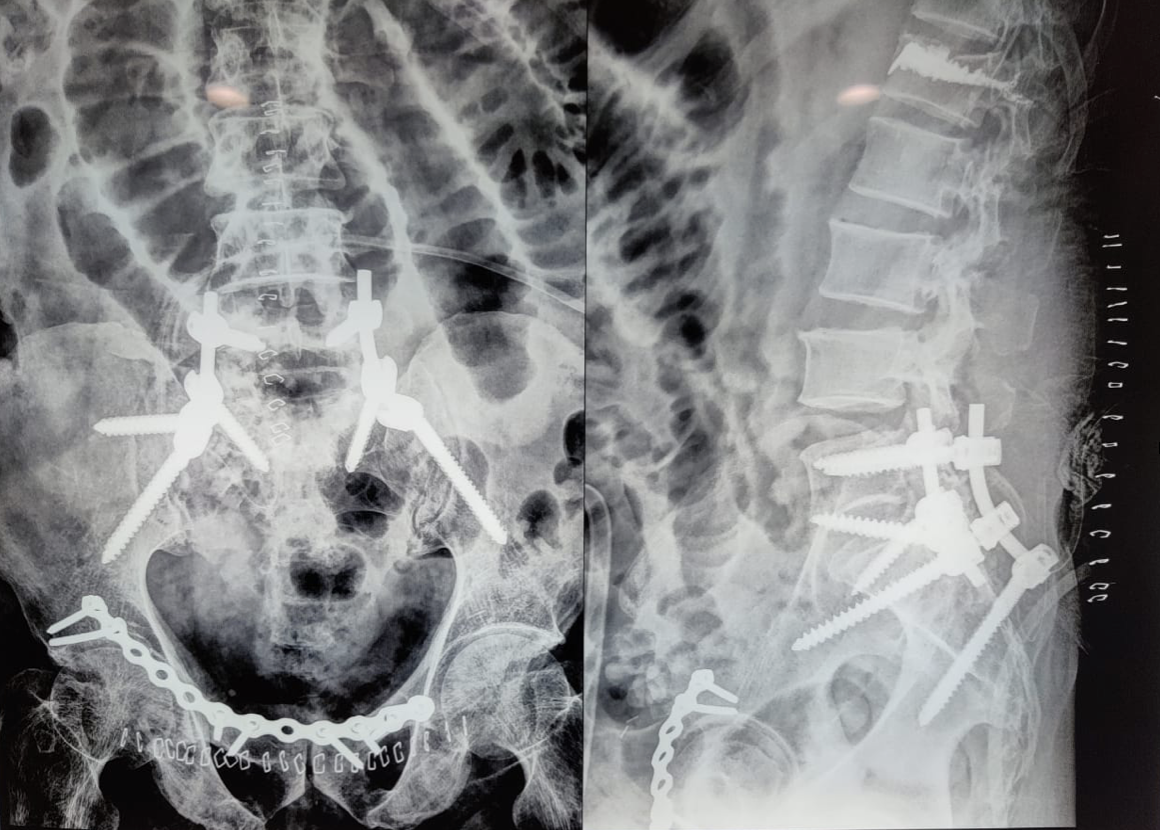

In addition, a Morel-Lavallée lesion was noted near the right kidney and was subsequently debrided with a drain in place. Initial ultrasound imaging of the abdomen revealed minimal free fluid, and the patient was stabilized with hemoglobin levels raised to 10 g/dL. Surgical intervention began with stabilization of the spine through open reduction and internal lumbo-pelvic fixation. The patient was then repositioned to fix the right acetabular fracture using a modified Stoppa approach (Fig. 2).

Figure 2: Post-operative X-ray of lumbopelvic fixation (L5-Iliac); L1 vertebroplasty; Right acetabulum anterior column open reduction internal fixation with 14-hole Recon plate.